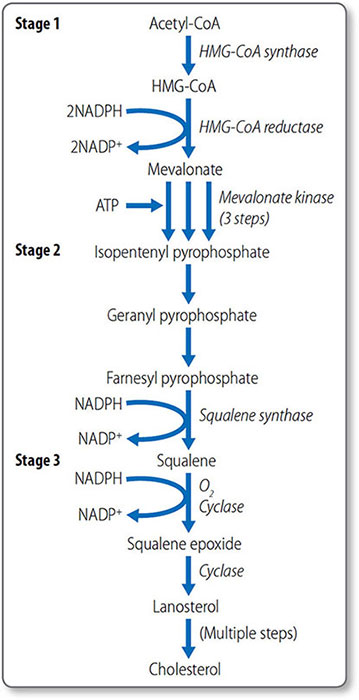

Cholesterol synthesis

Cholesterol biosynthesis begins with formation of isopentenyl pyrophosphate from acetyl CoA (Figure 1.46). The first step is the condensation of acetyl CoA with acetoacetyl CoA, forming 3-hydroxy-3-methylglutaryl CoA (HMG-CoA), a reaction catalyzed by HMG CoA synthase.

Formation of mevalonate HMG-CoA, which is present in the cytosol and mitochondria of the liver, is reduced to mevalonate by HMG-CoA reductase. This reaction requires NADPH. This is the first irreversible, committed step of cholesterol synthesis. Mevalonate is then converted to isopentenyl pyrophosphate in a series of three ATP-dependent reactions.

Synthesis of squalene The second stage of cholesterol synthesis is the synthesis of squalene, a 30-carbon hydrocarbon molecule, from five five-carbon molecules of isopentenyl pyrophosphate.